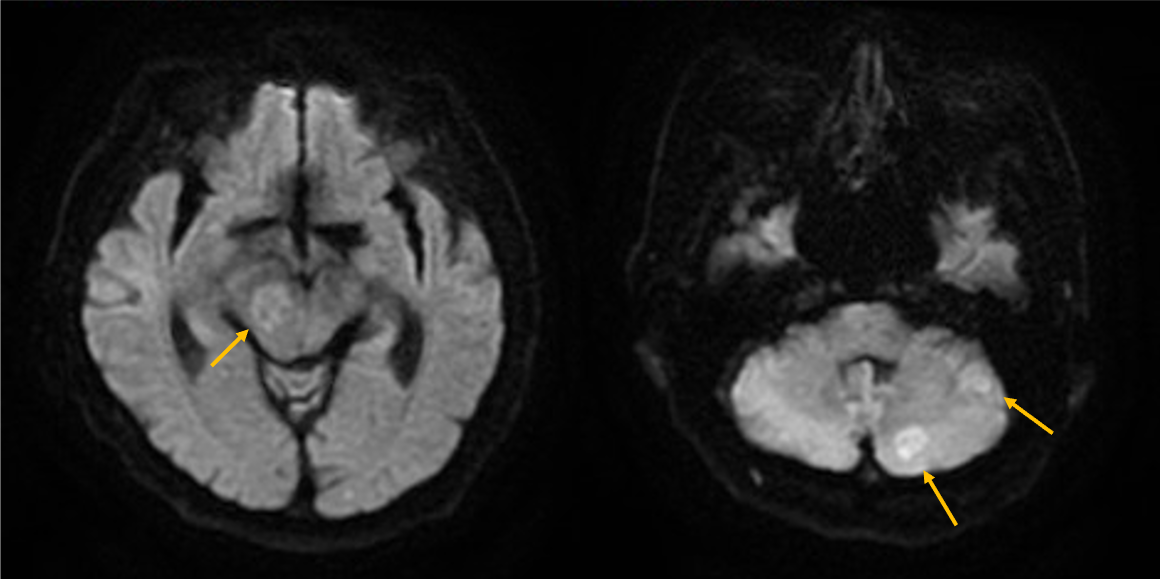

症例は70歳代男性。物が二重に見える、ふらつくとの訴えで来院。非造影MRIにて脳幹部や小脳に4個の多発脳腫瘍が認められ、症状と合致した。全身精査にて進行胃癌が発見され、その脳転移と診断された。放射線治療の適応判定のため造影MRIを施行し、新たに大脳に3個の微小転移が同定された。病変のサイズ・分布から微小転移を含む7個の腫瘍に対して定位放射線治療が可能と判断され、速やかに治療導入に至った。

本症例では先行する非造影MRIにて右中脳や左小脳の多発腫瘤が指摘され、周囲に浮腫を伴うことから転移が疑われていたが、病変数や大きさ・範囲ははっきりしなかった。造影MRIを実施することにより、右中脳に1個、左小脳に3個の2㎝大の輪郭の明瞭な腫瘍が確認されたほか、1㎝未満の3個の微小病変を新たに検出できた。非造影MRIを見直したところ7㎜の結節はFLAIRでも淡い高信号を示していたが質的診断は困難であった。3㎜の病変は非造影MRIでは存在診断不能であった。微小病変のうち2個は高位前頭葉の機能的に重要な部位に位置しており、治療適応と考えられた。造影MRIにより腫瘍の正確な個数とサイズ、分布の正確な情報を確認した後、定位放射線治療が可能と判断され、3D-FSPGR画像を治療計画に利用して迅速に治療が開始された。